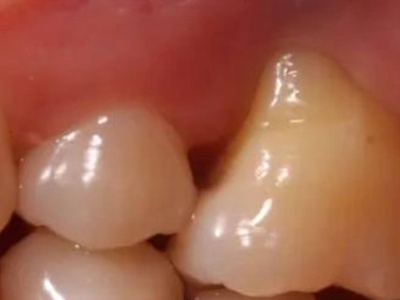

牙龈退缩牙根几乎整个暴露图

牙龈退缩患者的上排牙中一颗牙齿的牙根几乎整个暴露在外,暴露牙根的牙齿在受到冷热刺激时会格外敏感,伴有口臭、牙齿松动等症状。